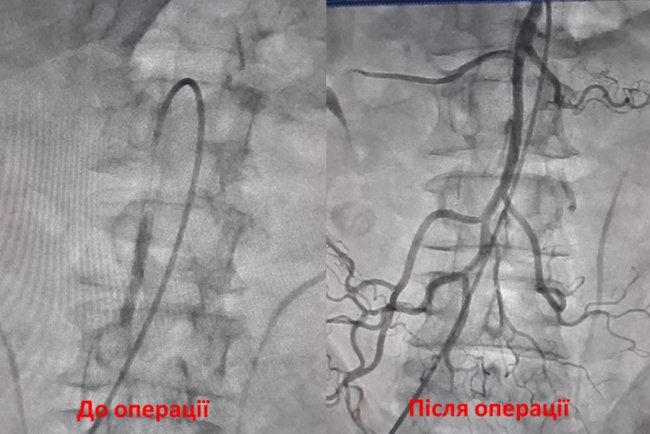

Волинські лікарі провели надскладну операцію з видалення тромбу. ФОТО

У Ковелі хірурги видалили тромб та відновити кровотік кишківника пацієнта.

"Бригадою наших ендоваскулярних хірургів проведено надскладну операцію з приводу гострого тромбозу верхньої брижової артерії. Під контролем ангіографа здійснено тромбоекстракцію (видалили тромп) та відновили кровотік кишківника (провели балонну ангіопластику та стентування верхньої брижової артерії)", - йдеться у повідомленні.

Тромбоз мезентеріальних судин, зокрема і верхньої брижової артерії – одна з найскладніших проблем серед ургентних захворювань органів черевної порожнини. Навіть у високоспеціалізованих клініках летальність при цій патології сягає 75—96%.